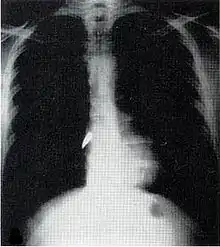

Assessment and treatment

Assessment can be difficult because much of the damage is often internal and not visible.[4] The patient is thoroughly examined.[2] X-ray and CT scanning may be used to identify the type and location of potentially lethal injuries.[2] Sometimes before an X-ray is performed on a person with penetrating trauma from a projectile, a paper clip is taped over entry and exit wounds to show their location on the film.[2] The patient is given intravenous fluids to replace lost blood.[2] Surgery may be required; impaled objects are secured into place so that they do not move and cause further injury, and they are removed in an operating room.[2] If the location of the injury is not obvious, a surgical operation called an exploratory laparotomy may be required to look for internal damage to the organs in the abdomen.[17] Foreign bodies such as bullets may be removed, but they may also be left in place if the surgery necessary to get them out would cause more damage than would leaving them.[12] Wounds are debrided to remove tissue that cannot survive and other material that presents risk for infection.[2]